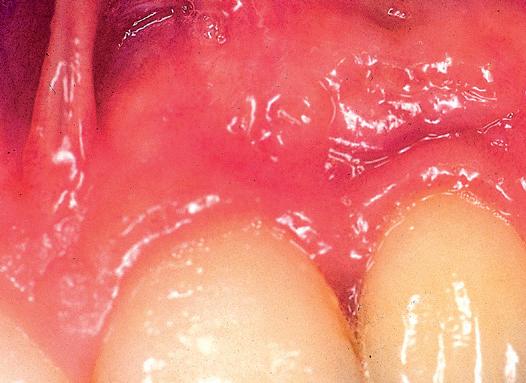

Se realizó un autoinjerto libre epitelizado submarginal, es decir, respetando la pequeña banda de encía queratinizada existente, con la técnica de injerto en acordeón que se extendió de 33 a 43. La gura nº 7, muestra la cicatrización temprana. Como era de esperar, se ha logrado aumentar la cantidad de encía insertada,

por debajo del margen gingival, situándose éste en su posición original. Lo llamativo de este caso es que, transcurridos 12 años, la encía ha migrado hacia incisal y ha cubierto parcialmente las super cies radiculares expuestas (Fig nº 8). Es curioso observar cómo con el transcurso de los años se ha remodelado el tejido blando, otorgándole un contorno y un volumen muy diferentes a los que se aprecian en la gura nº 7.

Fig 7: Cicatrización temprana. Se realizó un autoinjerto submarginal. Se aprecian de manera nítida los límites que de nen el injerto y el margen gingival que ha sido respetado. El injerto, ha logrado crear una adecuada dimensión volumétrica de encía insertada y ha profundizado el vestíbulo. En ningún momento se ha pretendido cubrir la super cie radicular.

Fig 8: Resultado a los 12 años. Compárese con la Fig 7. El injerto ha sufrido un profundo remodelado con el paso del tiempo, modi cándose su contorno, volumen y cubriendo parcialmente las super cies radiculares expuestas. ¿Cómo es posible que ocurra este fenómeno con un injerto submarginal?